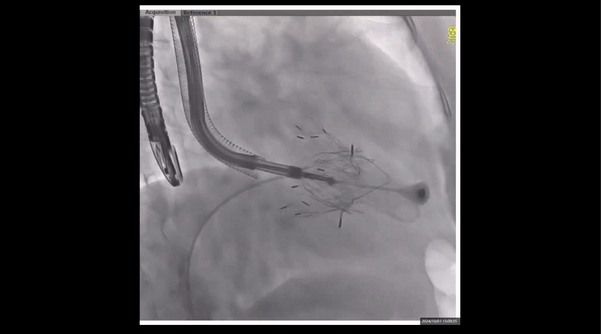

術(shù)前右室造影

夾持件位置確認(rèn)

室間隔位置確認(rèn)

瓣膜釋放